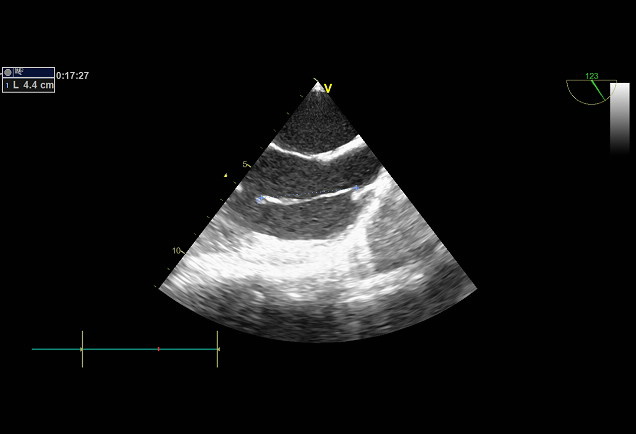

Palpitations !

Mme XX âgée de 40 ans, sans ATCD particuliers, symptomatique de palpitations gênantes.

L’ECG s’inscrit en RS, pas de trouble de conduction pas de trouble de repolarisation.

L’holter rythmique n’a pas objectivé de trouble rythmique.a